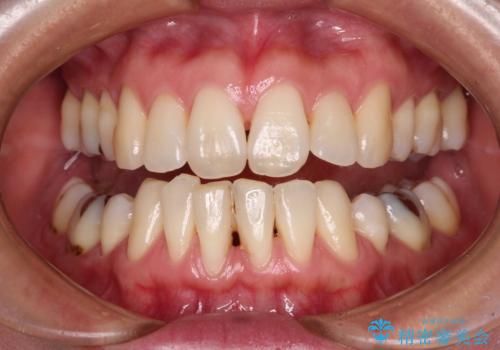

歯と歯と歯肉の間にある三角形の隙間(ブラックトライアングル)は歯肉移植では改善できないため、根面被覆できる量に限界がありましたが、最大限回復させることができました。